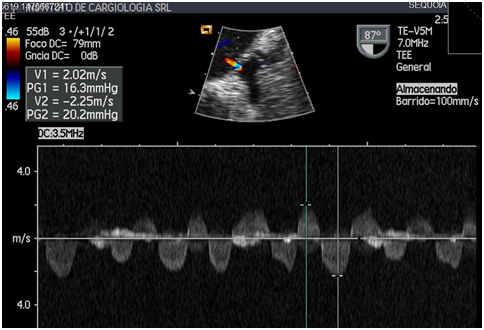

Figure 5 Spectral doppler showing high emptying and filling velocities of the left atrial appendage. You can see speeds above 2 meters per second.